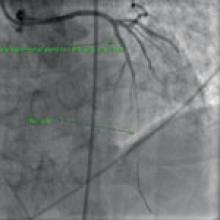

Canada is spearheading an international study to determine if an implantable cardioverter defibrillator (ICD) can prevent death from serious heart rhythm problems in those patients who’ve survived a heart attack. Heart disease is a leading cause of death in Canada and the fastest growing disease worldwide.